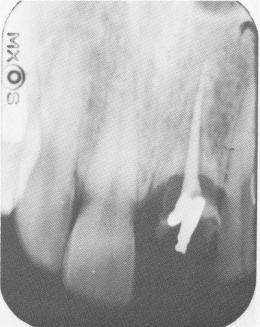

Fig. 8-32. The radiograph shows complete resorption of a reimplanted central incisor. Only the gutta-percha point and a minute amount of tooth structure remain, covered with an acrylic jacket that cannot be seen in the radio-graph.